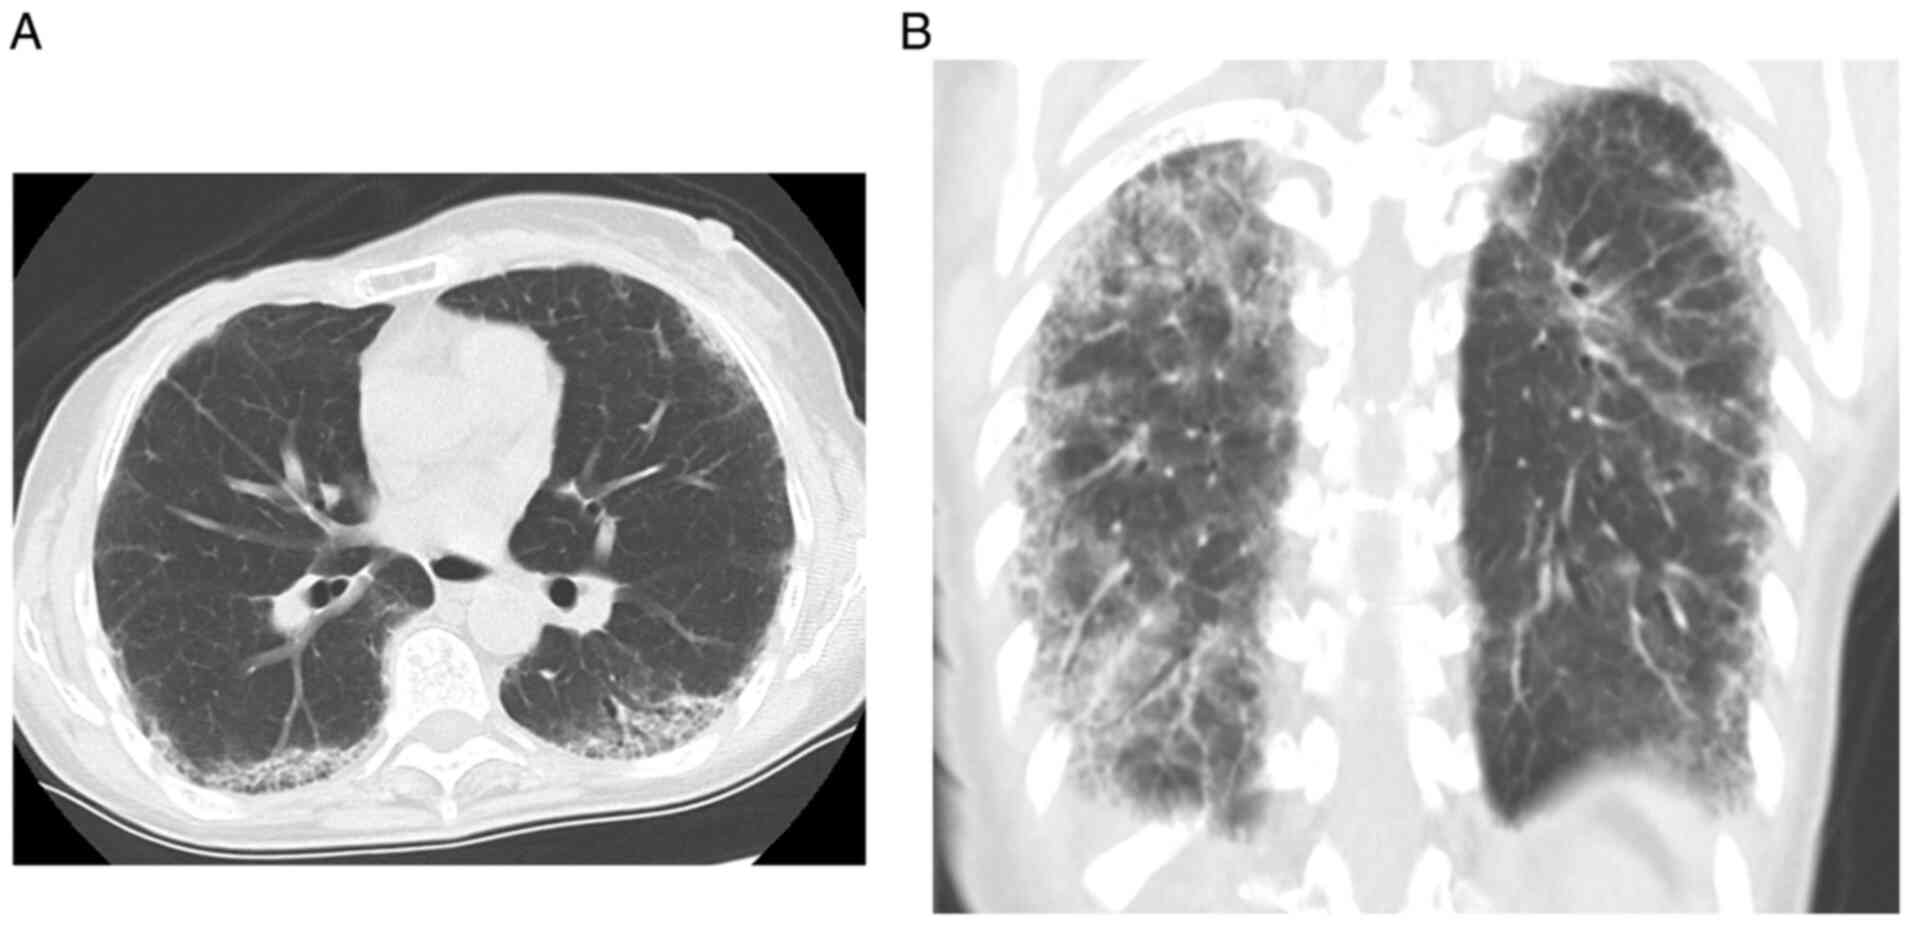

At 63 years old, contrast-enhanced computed tomography (CT) performed as postoperative follow-up indicated brain metastasis in the right occipital lobe without liver, lung, or bone metastasis. She underwent γ-knife radiosurgery (20 Gy) followed by the administration of perutuzumab, trastuzumab, and weekly paclitaxel. After four cycles of perutuzumab, trastuzumab, and weekly paclitaxel, she experienced shortness of breath with minimal exertion, so the fifth course was canceled. CT revealed ground-glass opacities and linear shadows in the peripheral lower lobes of both lungs (Fig. 1). Although the development of lung involvement associated with breast cancer such as carcinomatous lymphangitis was initially suspected, because of the increase in CA 15-3, we investigated other possible causes of ILD (Fig. 2). From only CT image, the possibility of interstitial lung disease due to trastuzumab or pertuzumab cannot be ruled out (19). Bilateral sclerodactyly and facial skin thickness were found on clinical examination without a history of Raynaud's phenomenon and the finding of nail fold bleeding. A test for anti-nuclear antibodies with a nucleolar pattern was positive, at a titer of 1:320. Anti-double stranded DNA antibody, specific antibodies against centromere, SSA/SSB, Scl-70, RNP, and RNA polymerase III were negative. Pulmonary function tests showed a severely reduced %VC of 50.8%, indicating restrictive ventilatory impairment. Skin biopsies taken from the left index finger base and extension side of the left elbow demonstrated increased thickness of the dermis composed of broad and sclerotic collagen bundles extending to the underlying subcutis without inflammatory cell infiltration in hematoxylin and eosin stained-samples. These findings were consistent with the late stage of scleroderma (Fig. 3). From these findings, the diagnosis of SSc-ILD was made according to the diagnostic criteria for SSc proposed by the Ministry of Health, Labour and Welfare of Japan. The treatment for recurrent breast cancer was discontinued, and combination prednisone (PSL) (15 mg/day) and intravenous cyclophosphamide (IVCY) (500 mg/4 weeks) therapy was administered for induction treatment of SSc-ILD. PSL was tapered and discontinued at 1 year and IVCY was given five times in total. At 6 months after the start of treatment, her symptoms, including cough and dyspnea, had improved. CA 15-3 and KL-6 levels decreased simultaneously, reflecting the therapeutic effect (Fig. 2), and CT showed improvement in the ground-glass opacities in the peripheral lower lobes of both lungs as compared with those before treatment (Fig. 4). This patient is receiving treatment for SSc-ILD. The patient's SSc-ILD has not worsening and her breast cancer has not recurred despite not receiving treatment for four years.

Figure 1

Chest computed tomography reveals ground-glass opacities and linear shadows in the peripheral lower lobes of both lungs. (A) Axial section view, (B) coronal section view.